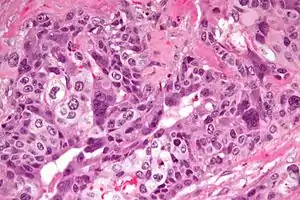

| Micrograph of choriocarcinoma showing both of the components necessary for the diagnosis - cytotrophoblasts and syncytiotrophoblasts. The syncytiotrophoblasts are multinucleated and have a dark staining cytoplasm. The cytotrophoblasts are mononuclear and have a pale staining cytoplasm. H&E stain. | |

Characteristic feature is the identification of intimately related syncytiotrophoblasts and cytotrophoblasts without formation of definite placental type villi. Since choriocarcinomas include syncytiotrophoblasts (beta-HCG producing cells), they cause elevated blood levels of beta-human chorionic gonadotropin.

Syncytiotrophoblasts are large multi-nucleated cells with eosinophilic cytoplasm. They often surround the cytotrophoblasts, reminiscent of their normal anatomical relationship in chorionic villi. Cytotrophoblasts are polyhedral, mononuclear cells with hyperchromatic nuclei and a clear or pale cytoplasm. Extensive hemorrhage is a common finding.